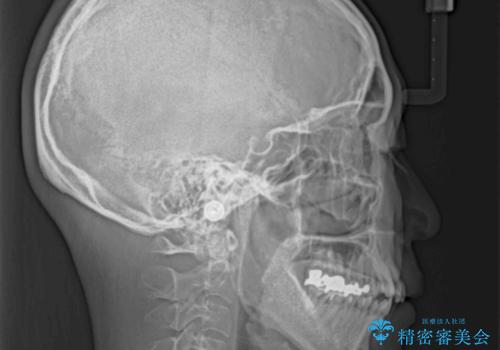

閉じにく口元と欠損歯列 ワイヤー装置の抜歯矯正

- 八重歯と前歯の隙間を気にして来院された患者様です。

下顎前歯は2本欠損しており、それが原因で隙間ができていました。

また、その影響で上下歯列がアンバランスとなっており、上下前が非接触となっていました。

上下のバランスを取って八重歯などを解消するため、上顎左右第1小臼歯を抜歯することとしました。

根管治療の必要な歯も2本あったため、まずは根管治療を行い、ワイヤー矯正の後に補綴治療を行うこととしました。

上顎左右第1小臼歯を抜歯したことで、隙間が閉じた下顎歯列の位置まで前歯を引っ込ますことができたため、口の閉じにくさを解消することができました。